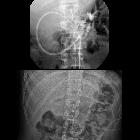

Teenager who

is having emesis during feeding through the jejunostomy port of his gastrojejunostomy tube. AXR taken after injection through the jejunostomy port of a newly placed gastrojejunostomy tube one month ago (above) shows the tip of the jejunostomy tube to be in the proximal jejunum. AXR taken today (below) shows that the tip of the jejunostomy tube has been pulled back into the antrum of the stomach.The diagnosis was gastrojejunostomy tube malfunction due to migration of the tip of the jejunostomy tube back into the stomach.